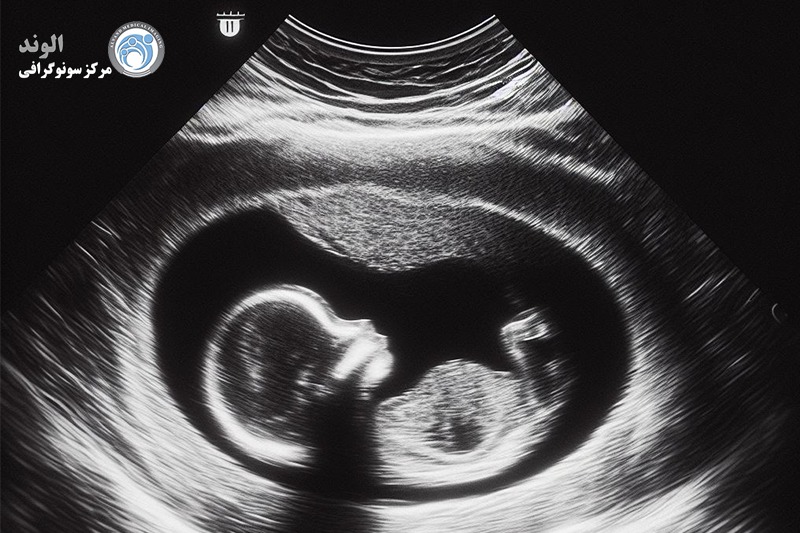

تصویربرداری دو بعدی هنوز استاندارد طلایی است و معمولاً در اکوکاردیوگرافی جنین استفاده می شود. بنابراین، ما نماهای استاندارد از قلب طبیعی جنین را که در سه ماهه دوم با سونوگرافی دو بعدی و داپلر موجی رنگی و پالسی به دست آمده است، ارائه می کنیم. ما همچنین یافتههای اکوکاردیوگرافی جنین در سه ماهه اول و یک شاخص عملکرد قلب اصلاح شد را ارائه میکنیم که ابزار مفیدی برای ارزیابی عملکرد قلب جنین است.

اکوکاردیوگرافی جنین آزمایشی شبیه به سونوگرافی است. این معاینه به پزشک شما اجازه می دهد تا ساختار و عملکرد قلب فرزند متولد نشده شما را بهتر ببیند. معمولاً در سه ماهه دوم، بین هفته های 18 تا 24 انجام می شود.

در این روش از سونوگرفی از امواج صوتی استفاده می شود و از ساختار قلب جنین "پژواک" می زند. یک دستگاه این امواج صوتی را برای پزشک تجزیه و تحلیل می کند و تصویر یا اکوکاردیوگرام از درون قلب نوزاد ایجاد می کند. این تصویر اطلاعاتی در مورد چگونگی شکل گیری قلب کودک شما و اینکه آیا به درستی کار می کند ارائه می دهد.

همچنین پزشک جریان خون را در قلب جنین به شما نشان می دهد. این نگاه عمیق به پزشک اجازه می دهد تا هر ناهنجاری در جریان خون یا ضربان قلب نوزاد وجود دارد را بیابد.